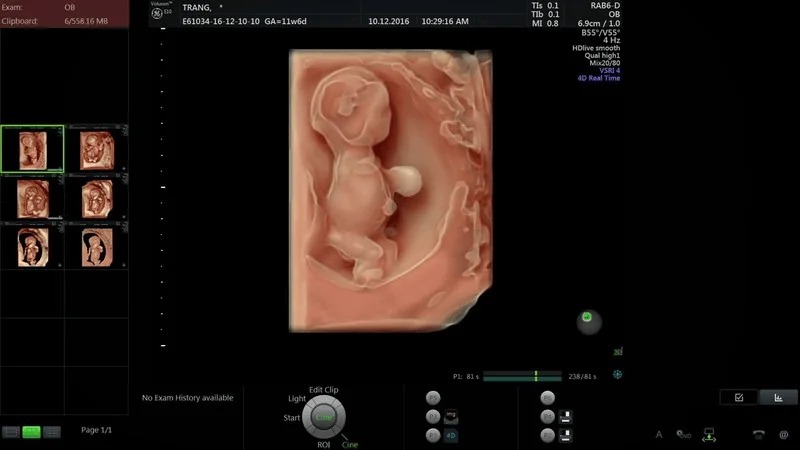

Thai nhi 12 tuần tuổi là thời điểm thích hợp để mẹ thực hiện siêu âm và kiểm tra một số chỉ số sức khỏe của con. Tại thời điểm này, thai nhi đã phát triển cơ bản đầy đủ về các chức năng của mọi hệ cơ quan, bắt đầu hình thành các giác quan, hệ cơ và các bộ phận của cơ thể. Hình ảnh thai 12 tuần cũng có thể giúp mẹ phát hiện những thay đổi bất thường của thai nhi nếu có để phòng ngừa dị tật bẩm sinh.

Thai 12 tuần phát triển mạnh mẽ với trọng lượng tăng gấp đôi tuần trước đó, có thể đạt từ 58g trở lên cùng kích thước 5,4 cm tương đương một quả mận lớn. Hệ thống tim mạch của bé cũng dần hoàn thiện về mặt chức năng.

Khá nhiều mẹ bầu thường thắc mắc thai 12 tuần đã máy chưa, vậy câu trả lời chính xác là gì? Thực tế, lúc này, cẳng tay và cẳng chân của bé bắt đầu vươn dài ra, có thể thực hiện một số cử động đơn giản khá linh hoạt như co, duỗi, nắm, đạp... Điều đó có nghĩa ở giai đoạn này, thai đã máy rồi.